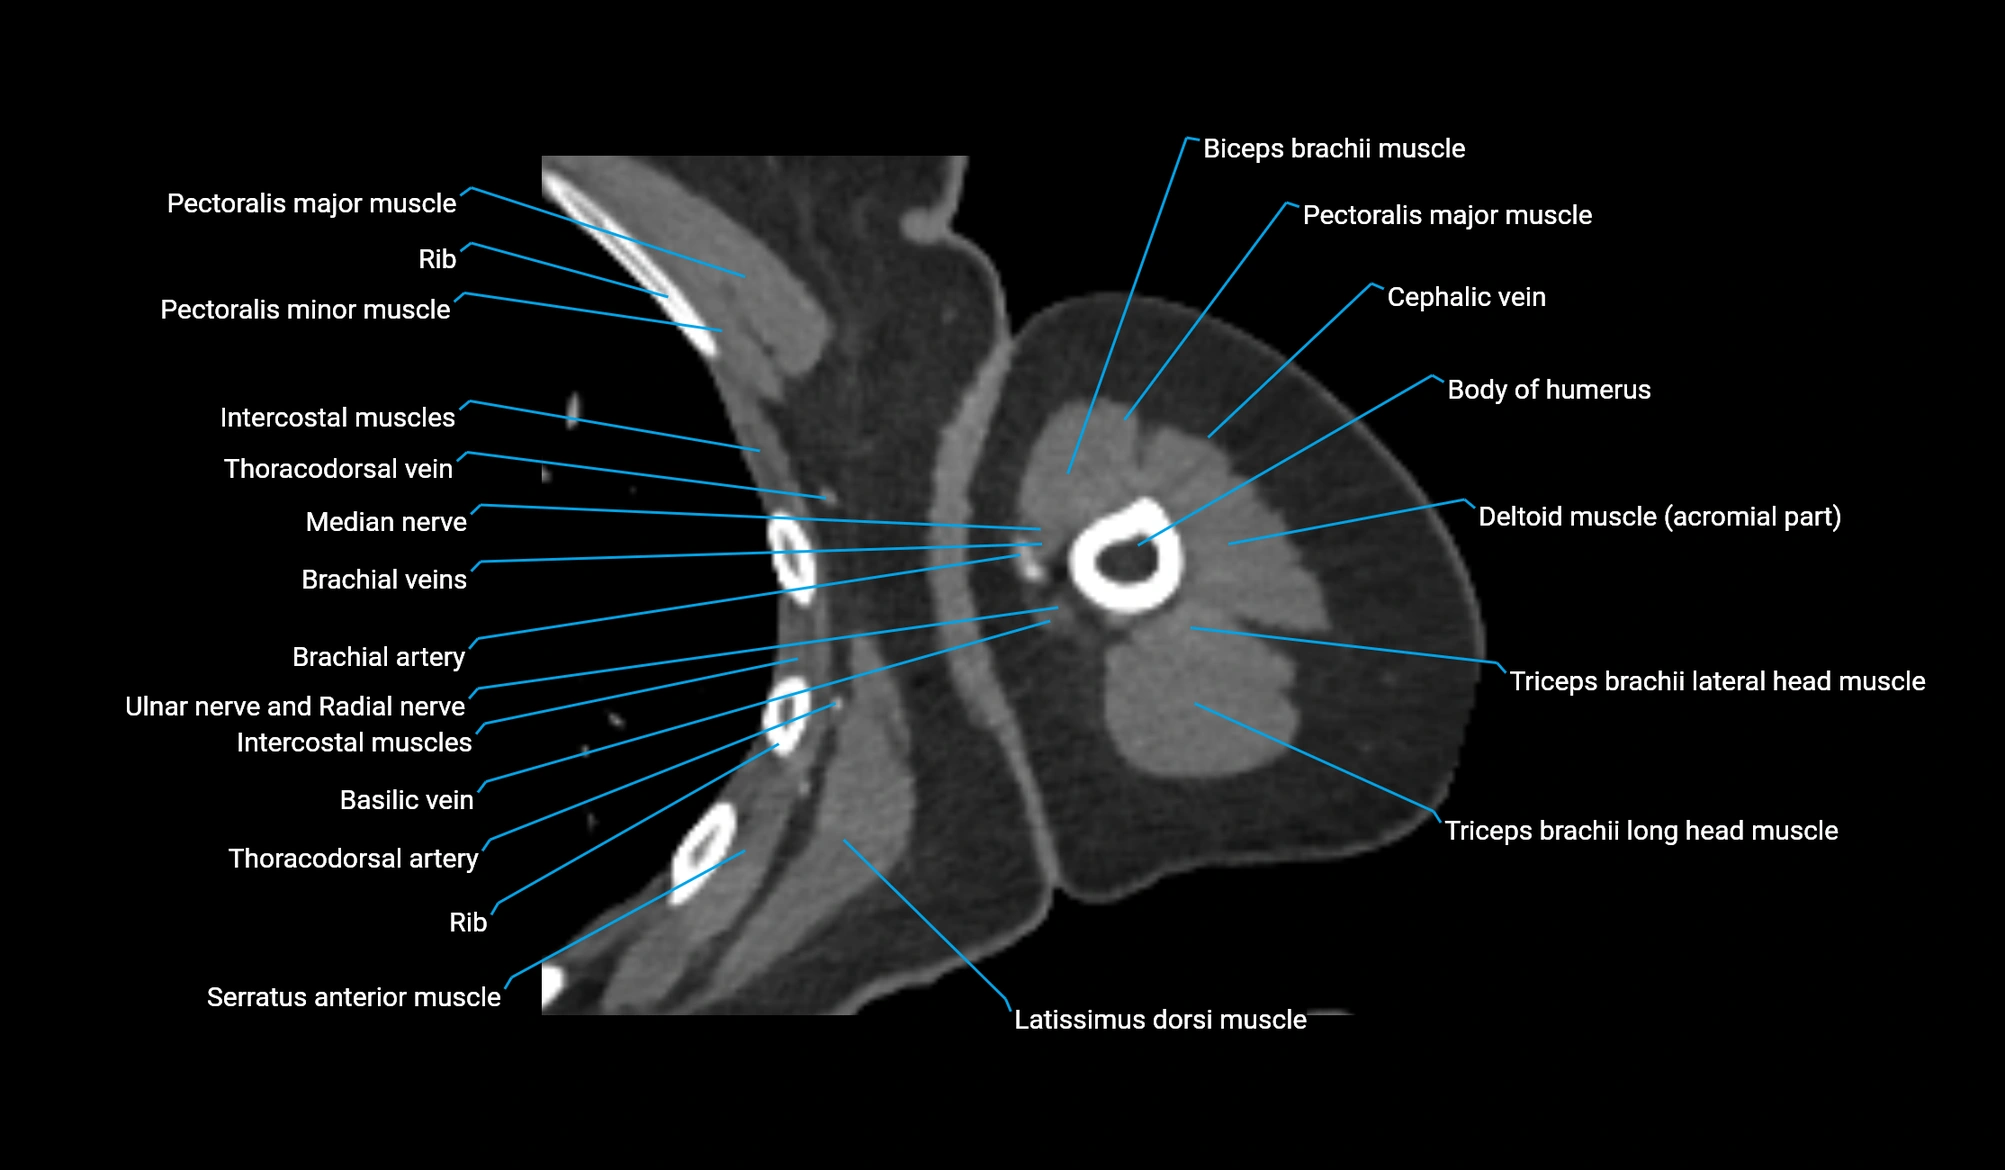

CT image